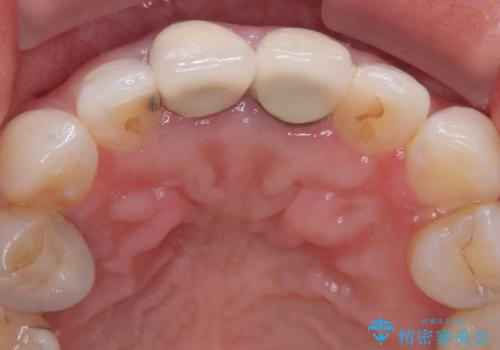

拡大鏡視野下で、被せもの、金属の土台、虫歯を除去し、ファイバーの土台(ファイバーコア)をたてて、オールセラミッククラウンに適した形に整えました。

患者様のご希望で周りの歯も白くしたいとのことでオフィスホワイトニング、ホームホワイトニングで色の調整を行い、色味が落ち着いてから、歯と歯茎の間に圧排糸と呼ばれる糸を入れてシリコーン印象を行いました。